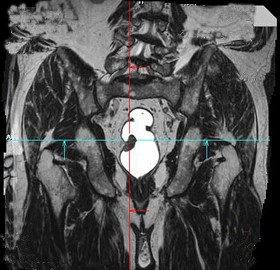

[单选题]男,70岁,下腹部腹胀、腹痛、排便困难,逐渐加重,MRI示直肠内不规则充盈缺损,最可能的诊断是A.直肠息肉B.直肠癌C.直肠间质瘤D.直肠转移癌E.直肠淋巴瘤

[单选题]男,70岁,下腹部腹胀、腹痛、排便困难,逐渐加重,MRI示直肠内不规则充盈缺损,最可能的诊断是()A .直肠息肉B .直肠癌C .直肠间质瘤D .直肠转移癌E .直肠淋巴瘤